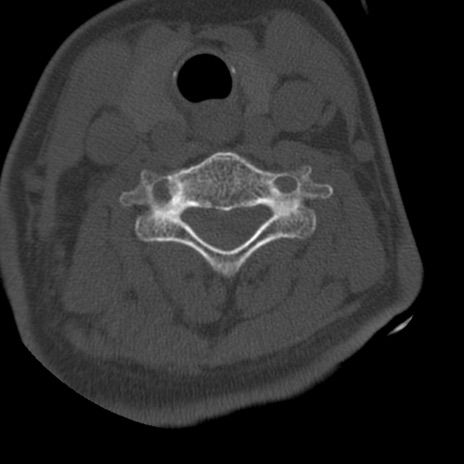

症例50 頚椎CT(横断像)

頚椎CT